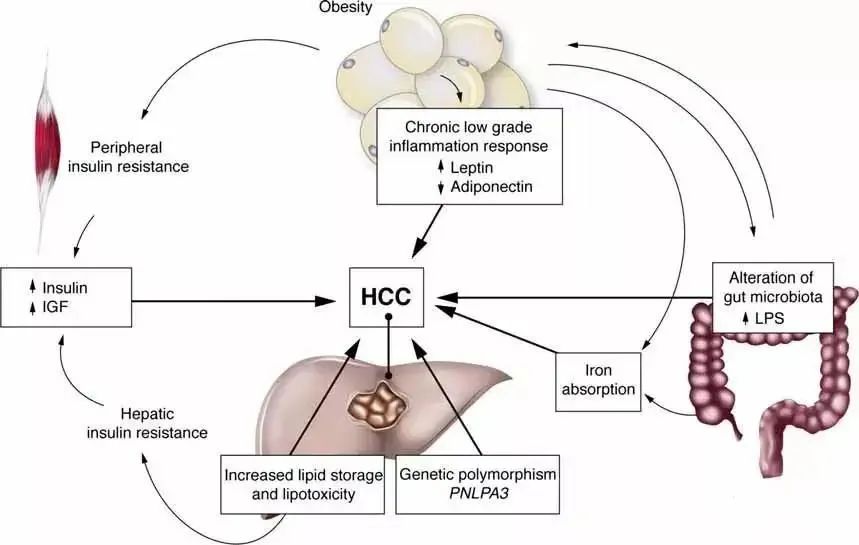

目前常規的乙肝治療是抑制乙肝病毒的復制,減少炎癥和壞死,從而延緩疾病的進展,但很難從根本上清除病毒,人們急需尋找到新的抗擊病毒性肝炎的治療方式。

間充質干細胞(MSCs)由于其分化潛能、免疫調節特性和旁分泌釋放作用而被認為是一種值得人們關注的的治療肝病的選擇。近年來,間充質干細胞在肝臟疾病中的應用引起了廣泛關注。

1、分化為功能性肝細胞:干細胞分化為肝細胞是干細胞用于肝病治療的理論支撐,干細胞向具有功能性肝細胞分化的潛能已經得到研究證實。

2、免疫調節:干細胞的免疫調節特性會對肝病產生有利影響,如調節炎癥反應中T細胞、B細胞等免疫細胞的活化增殖。

3、抗纖維化 :干細胞通過間接或直接細胞接觸抑制肝星狀細胞的活化增殖,減少膠原蛋白的沉積,阻止肝纖維化進一步發展為肝硬化。

干細胞具有自我更新復制和增殖能力,并有多向分化潛能,進入人體后會自動分化成各種細胞,從而對各系統出現異常的細胞進行全面修復和更新,使人體內部各臟器的亞健康得到改善并恢復健康。